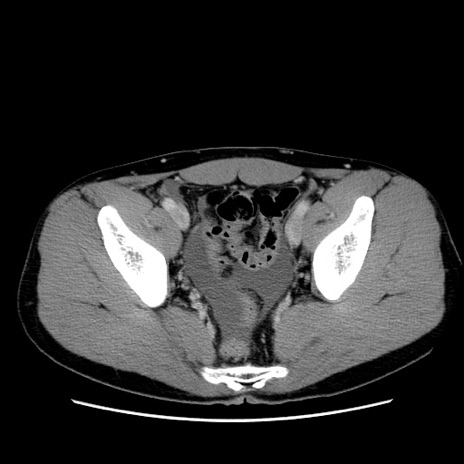

症例36(横断像)

【症例】20歳代 男性

【主訴】心窩部痛

【現病歴】今朝より上腹部痛あり。一旦軽快していたが再度出現したため救急要請。昨日夕に白身の魚を含む刺身を食べた。

【身体所見】BP 136/89mmHg、HR 74/min、BT 37.0℃、腹部:膨満、軟、心窩部に圧痛あり。反跳痛なし、筋性防御なし、腸雑音やや亢進あり。

【データ】WBC 17700、CRP 0.48